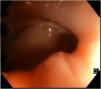

Following the evaluation protocol, diagnostic colonoscopy was performed, in which an ulcerated stricture was revealed at the level of the hepatic flexure, preventing the passage of the endoscope (Fig. 1), and was suggestive of a neoformation. Biopsy specimens were taken, and tattooing was applied, in a distal direction. Only uncomplicated diverticula were observed in the rest of the examination.

During colonoscopy, the most frequent finding is that of irregular, nodular, erythematous, and edematous mucosa, with areas of ulceration,5,7,9 which is different from that observed in Crohn’s disease, in which the mucosa surrounding the ulcers usually appears normal.